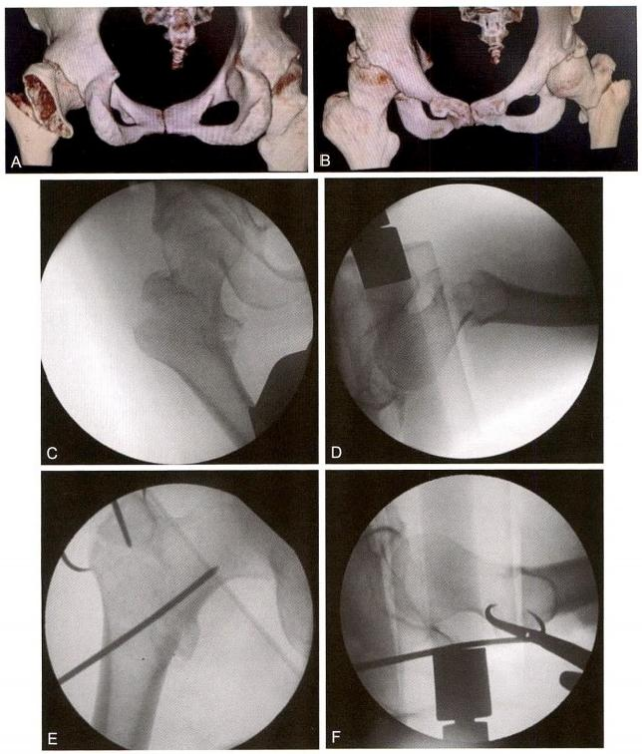

图9-11 难复型病例。A 、B.术前CT;C. 牵引后正位示复位不良,近端矢状位旋前;

D. 牵引后侧位复位不良,近端向前移位;E 、F. 采用多种复位方法后

4)术中复位技巧4:对于难复型病例,可以综合运用多种方法复位, 此类简单骨折(AO 分型A1.2, 即2007版的A1.3) 复位非常困难。往往 由于复位不良,导致手术失败(图9-11A 、B); 牵引后正位复位不良, 近端矢状位旋前(图9-11C); 牵引后侧位复位不良,近端向前移位(图 9-11D) 。用点状复位钳钳夹复位,正、侧位良好,并用克氏针临时固定, 然后常规髓内钉导针定位(图9-11E、F)。复位之后,需采用复位质量标准进行评价(表9-3、表9-4)。在开口 之前,不可接受的复位需要继续调整。